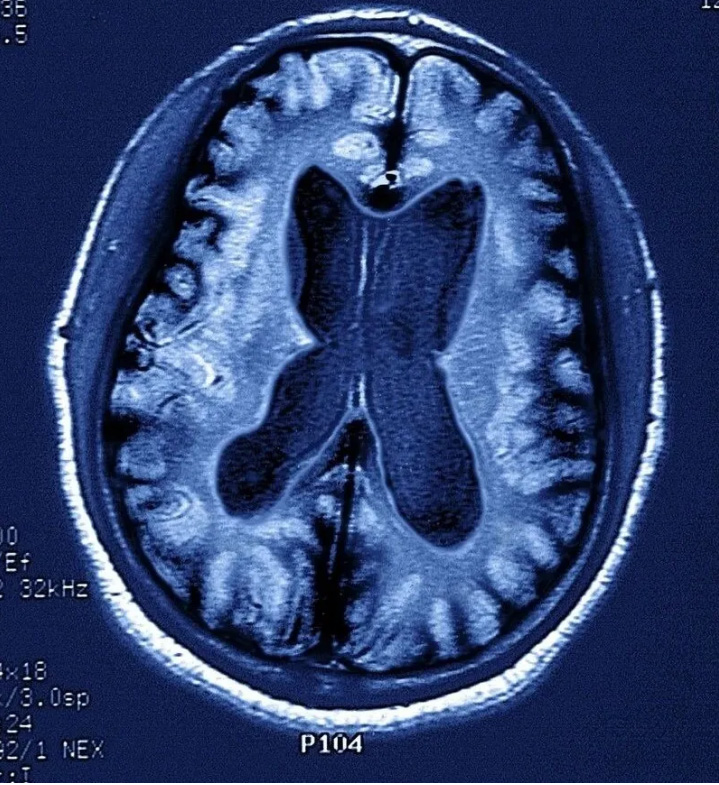

一般來說,記憶力下降是失智癥的核心癥狀,但它不是診斷失智癥的充分條件,目前臨床上診斷失智癥還要結合其它手段,如一系列的量表評估,MRI等客觀檢查。

因而當記憶出現問題時,可就診于各大醫(yī)院神經內科記憶門診,完成一系列的神經心理學量表測試、抽血檢查(查APOE ε基因型等)、腰穿腦脊液檢查(Aβ1-42的檢測)、尿和便標本、普通頭顱核磁,如有必要還需做PET-MRI以檢測腦內淀粉樣蛋白沉積。通過上述的綜合測試評估病情,給予診療意見。